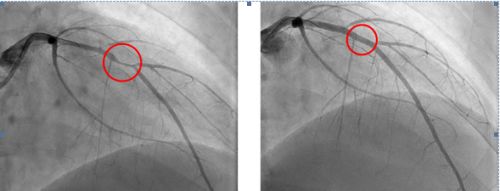

放置架前,血管严重狭窄(左);放入冠脉支架后,血管狭窄得到解决(右)。

2019年9月6日,18岁的湖南郴州小伙子小浩吃晚饭时突然感到胸痛、胸口发闷、呼吸困难,在家人陪同下立即赶到湖南省人民医院胸痛中心就诊。诊断为急性心肌梗死,被送往介入手术室。急诊造影发现:冠状动脉血管严重狭窄,需在体内植入心脏支架。

18岁,人生才刚刚开始就要带上心脏支架生活?心内科主任郑昭芬组织团队会诊后,建议小浩植入可吸收心脏支架,这种生物支架几年后就能降解。在征得小浩本人和家人同意后,心内三科主任潘宏伟等利用血管内超声引导,顺利为他植入一枚生物可吸收心脏支架,拆除了其体内的“炸弹”。